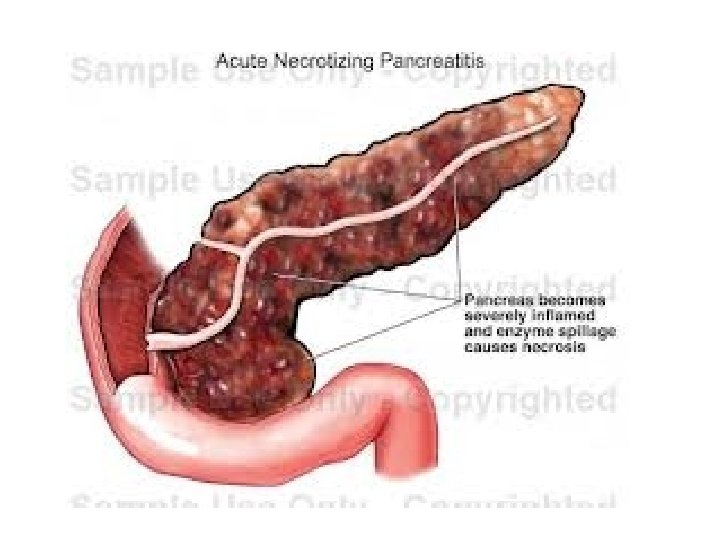

• KOMPLIKACIONET: - Kolecistit i supuruar (empiem i kolecistes) Perforim i kolecistes Pankreatit Kolangit Sepsis

• DIAGNOZA DIFERENCIALE: - Appendisiti (ne fazen fillestare) - Pankreatiti - Patologjite renale dexter: infeksion apo kalkul ne ureter: *Anamneza *Ekzaminime laboratorik (urine) *Ekzaminime radiologjike te aparatit urinar